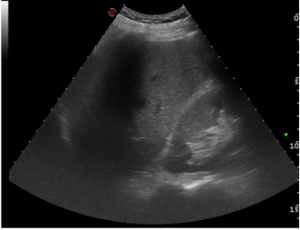

In the course of this imaging, a thin anechoic strip was noticed around the gallbladder

This pericholecystic fluid collection rapidly increased in size on serial FAST examination after 5 min.